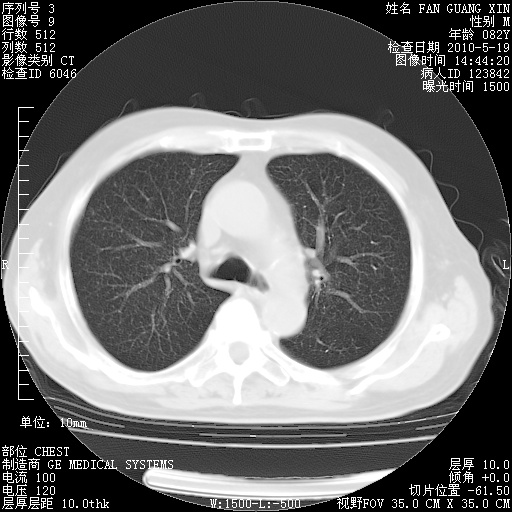

可改为口服强的松40-50mg/d治疗,若病情仍稳定,胸部阴影不再吸收可逐渐减量